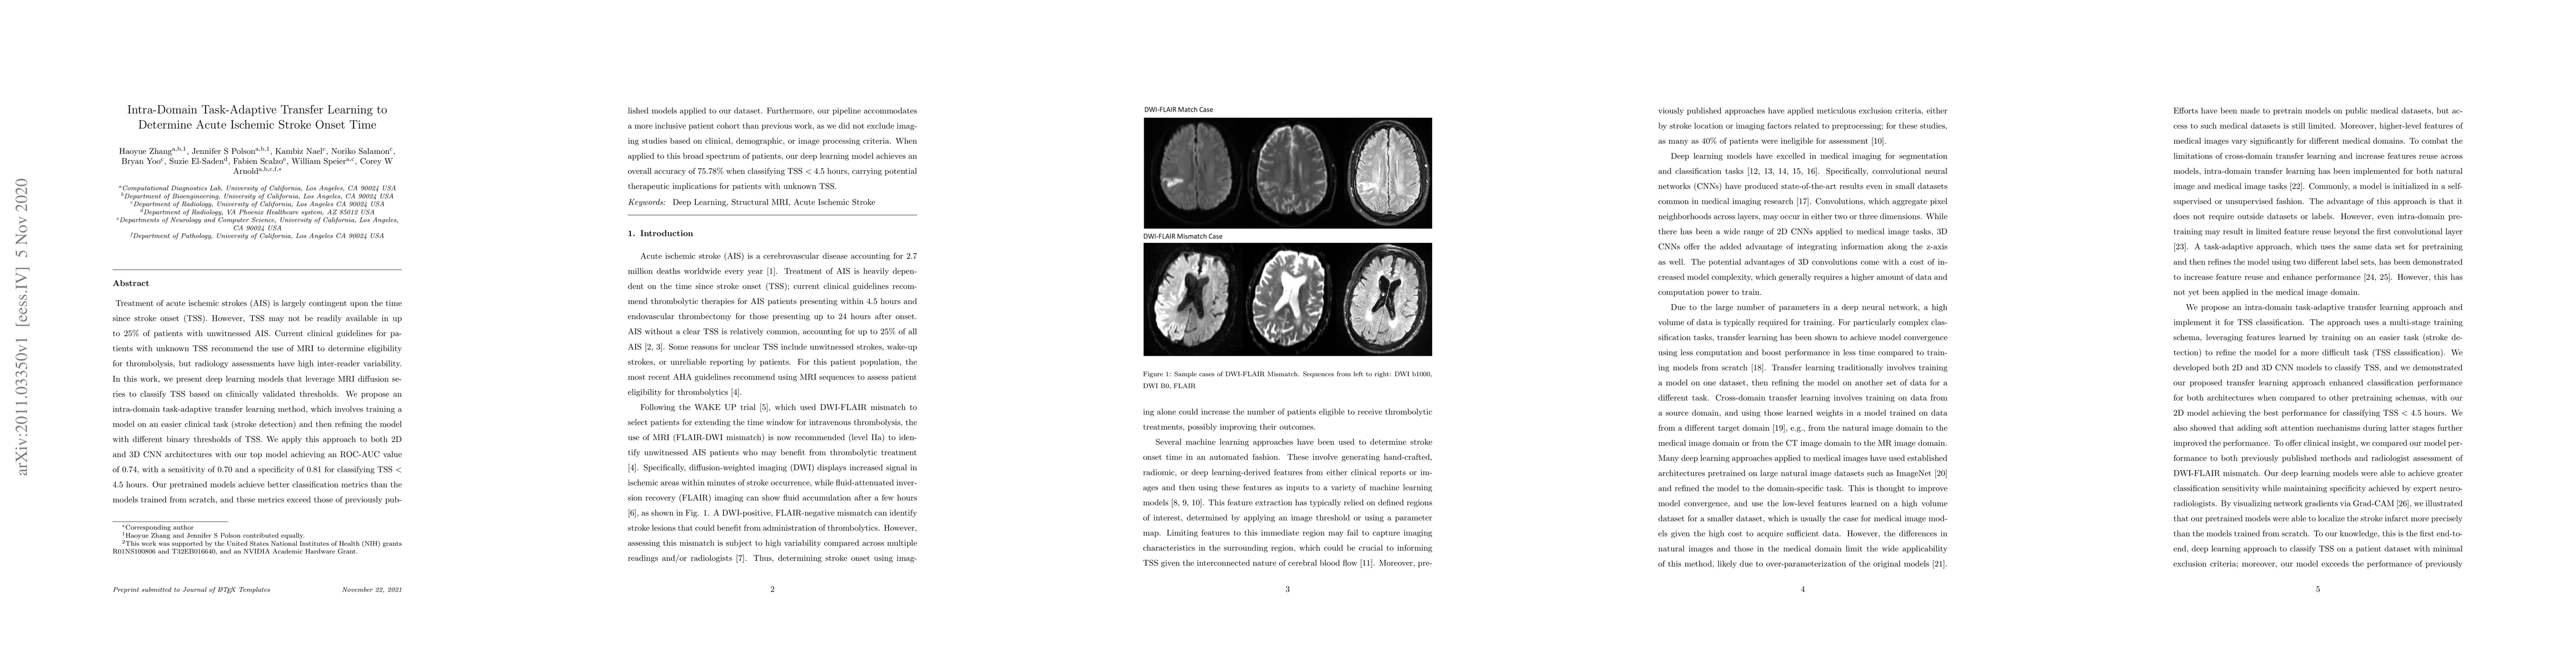

Treatment of acute ischemic strokes (AIS) is largely contingent upon the time since stroke onset (TSS). However, TSS may not be readily available in up to 25% of patients with unwitnessed AIS. Current clinical guidelines for patients with unknown TSS recommend the use of MRI to determine eligibility for thrombolysis, but radiology assessments have high inter-reader variability. In this work, we present deep learning models that leverage MRI diffusion series to classify TSS based on clinically validated thresholds. We propose an intra-domain task-adaptive transfer learning method, which involves training a model on an easier clinical task (stroke detection) and then refining the model with different binary thresholds of TSS. We apply this approach to both 2D and 3D CNN architectures with our top model achieving an ROC-AUC value of 0.74, with a sensitivity of 0.70 and a specificity of 0.81 for classifying TSS < 4.5 hours. Our pretrained models achieve better classification metrics than the models trained from scratch, and these metrics exceed those of previously published models applied to our dataset. Furthermore, our pipeline accommodates a more inclusive patient cohort than previous work, as we did not exclude imaging studies based on clinical, demographic, or image processing criteria. When applied to this broad spectrum of patients, our deep learning model achieves an overall accuracy of 75.78% when classifying TSS < 4.5 hours, carrying potential therapeutic implications for patients with unknown TSS.